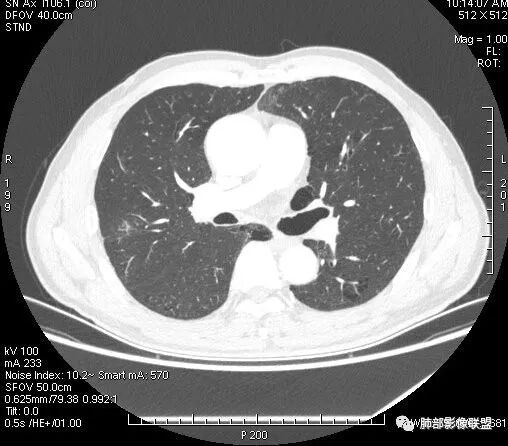

会是肿瘤吗?

1.病灶整体太圆,没有深分叶,没有粗短毛刺,收缩明显乏力,强化不显著等等缺乏典型肺腺癌的影像学特征。腺癌如此小病灶出现空洞更是匪夷所思!

2.肺鳞癌易坏死,可病灶如此小即出现影像学上可见的彻底的坏死空洞也非常少见。

病灶内“旁若无人”的血管走形也让人难以理解。而该疑问也存在于结核病灶的辨析当中。

会是感染吗?

病灶相对局限,或偏安肺野一隅,小病灶带空洞,最常见的还是感染。

注意这有别于某些广义的炎症,如血管炎、机化性肺炎等,以及一些全身性病损。

1.结核是常见的,坏死也够彻底,有卫星灶。疑问在于血管为什么不受累?

2.其他的慢性炎症。边界清楚符合慢性。慢性肺脓肿、隐球菌感染、奴卡菌感染等等都可以。可惜缺乏病原学依据。